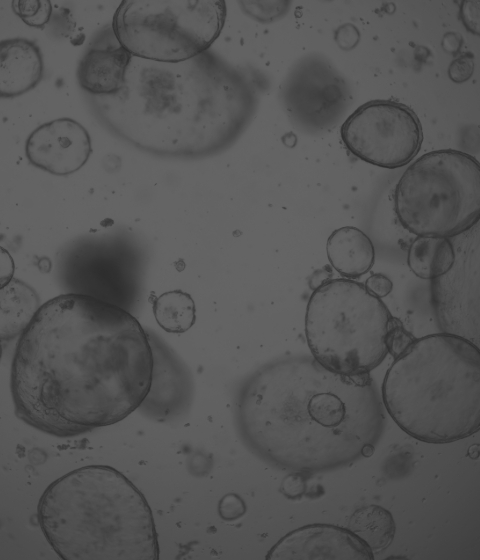

廈門模基生物科技有限公司致力于3D細(xì)胞培養(yǎng)核心原材料的研發(fā)與產(chǎn)業(yè)化升級(jí),是國內(nèi)一家從科研做起,從實(shí)驗(yàn)研究中一路走來的全流程自主研發(fā)、自主生產(chǎn)的企業(yè)。目前公司的產(chǎn)品有基質(zhì)膠、類器官培養(yǎng)基、細(xì)胞因子、3D細(xì)胞培養(yǎng)耗材、3D細(xì)胞培養(yǎng)智能顯微鏡等。公司擁有4大技術(shù)研發(fā)中心:分子克隆和細(xì)胞編輯中心、實(shí)驗(yàn)動(dòng)物中心、蛋白表達(dá)和純化平臺(tái)、類器官質(zhì)檢系統(tǒng)和自動(dòng)化。